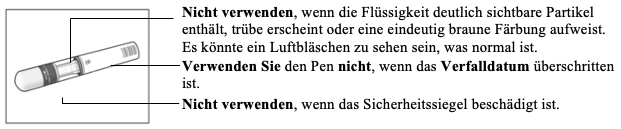

1. Wichtige Sicherheitskontrollen vor der Injektion:

Die Flüssigkeit sollte klar sein. Ihre Farbe kann farblos bis gelblich sein.

Wenden Sie sich an Ihren Apotheker, wenn der Pen eine dieser Sicherheitsanforderungen nicht erfüllt.